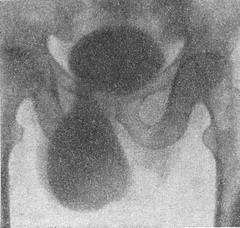

![]() Рис. 3. Пахово-мошоночная грижа сечового міхура (цистограмма). |

Грижі сечового міхура називають випадання його через грижові ворота (рис. 3). Частіше бувають пахвинні, пахові-мошоночние і стегнові грижі сечового міхура, рідше сідничні і промежностные.

Симптоми: грижове випинання, яке змінює свої розміри в залежності від ступеня наповнення сечового міхура, сечовипускання в два прийоми, затримка сечі, дизурія, піурія. Грижі сечового міхура виявляються за допомогою цистоскопії (див.) та цистографії. Лікування оперативне. Носіння бандажа протипоказано.